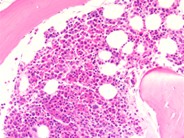

Systemic mastocystosis - 3.

The extent of the mast cell infiltrate is shown in this view, with the presence of large aggregates of these cells.